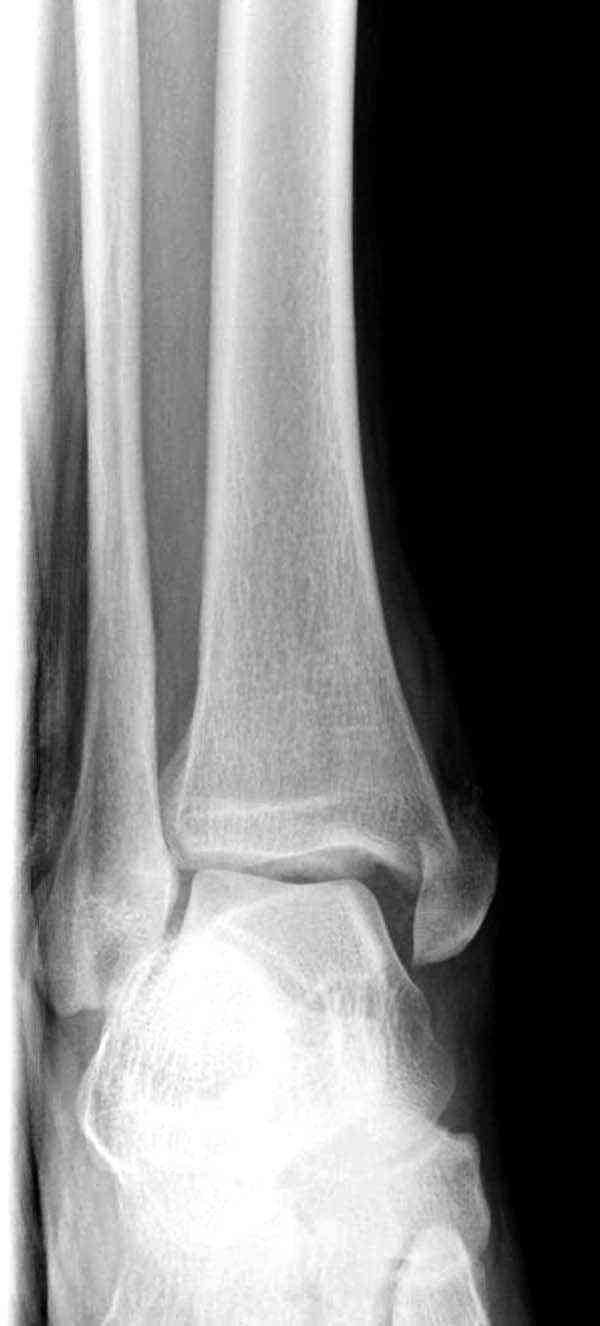

Внутренняя лодыжка

Вложение не в текстовом формате было извлечено…

Имя     : 3 Med mal fx Hook plate 000.JPG